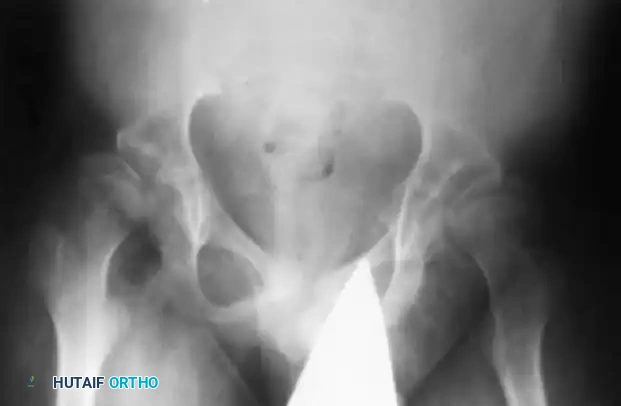

The classic radiographic presentation is severe coxa valga (an increased neck-shaft angle) combined with acetabular dysplasia, ultimately leading to subluxation or complete dislocation of the hip.

Fig. 32-25 Coxa valga deformity and subluxation in 12-year-old child with spinal muscular atrophy.

Paralytic Hip Dysplasia in SMA

Hip instability is a hallmark of severe SMA (Types I and II). The profound weakness of the gluteal and pelvic musculature, combined with the lack of normal weight-bearing forces, leads to a failure of normal proximal femoral and acetabular development.